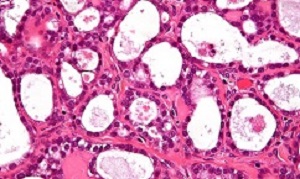

A team at the Institute of Cancer Research created an artificial intelligence (AI) tool that looks for clusters of cells within tumours with misshapen nuclei – the control centres within each cell. Women identified with these clusters of shape-shifting cells had extremely aggressive disease – with only 15% surviving for five years or more, compared with 53% for other patients with the disease.

The researchers found that having misshapen nuclei was an indication that the DNA of cancer cells had become unstable – and believe it could in future help doctors to select the best treatment for each patient.

Cancers with misshapen cell nuclei had hidden weaknesses in their ability to repair DNA, which could make them susceptible to drugs called PARP inhibitors or platinum chemotherapy. The researchers also found that immune cells were not able to move into the clusters of cells with misshapen nuclei, which suggests that cancers with these clusters are better at evading the immune system.

Scientists at The Institute of Cancer Research (ICR) applied their powerful new computer tool to automatically analyse tissue samples from 514 women with ovarian cancer – together looking at nearly 150m cells. The study funded by the ICR itself, used AI to look at the shape and spatial distribution of ovarian cancer cells and their surroundings.

The researchers found that tumours containing clusters of cells whose nuclei varied highly in shape had lower levels of activity of key DNA repair genes, including BRCA1. The test could be used to pick out tumours with lower levels of activity of DNA repair genes, even in cases where the genetic code of the BRCA genes remains intact. These hidden DNA repair defects would be overlooked when only testing for faults in DNA repair genes.

The presence of clusters was associated with even worse prognosis than mutations in the BRCA genes. The team at the ICR – a research institute and a charity – also found that the clusters had higher levels of a protein called galectin-3, which is known to cause key immune cells to die.

How tumor microenvironmental forces shape plasticity of cancer cell morphology is poorly understood. Here, we conduct automated histology image and spatial statistical analyses in 514 high grade serous ovarian samples to define cancer morphological diversification within the spatial context of the microenvironment. Tumor spatial zones, where cancer cell nuclei diversify in shape, are mapped in each tumor. Integration of this spatially explicit analysis with omics and clinical data reveals a relationship between morphological diversification and the dysregulation of DNA repair, loss of nuclear integrity, and increased disease mortality. Within the Immunoreactive subtype, spatial analysis further reveals significantly lower lymphocytic infiltration within diversified zones compared with other tumor zones, suggesting that even immune-hot tumors contain cells capable of immune escape. Our findings support a model whereby a subpopulation of morphologically plastic cancer cells with dysregulated DNA repair promotes ovarian cancer progression through positive selection by immune evasion.